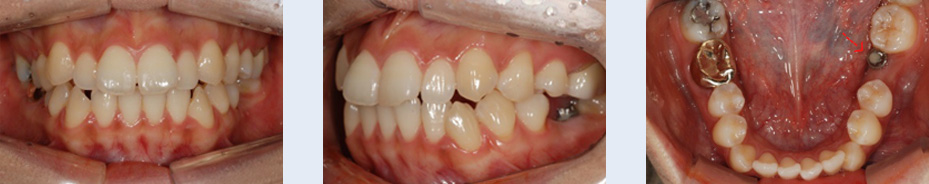

2년 전 식립한 임플란트의 보철물이 탈락된 상태로 1년간 지내오신 25세 여성입니다. 임플란트 식립을 위해

사용한 인공 뿌리를 제거하고 치아가 가지런해 지길 원하셨습니다. 자연치아로만 치료를 진행할 수 있도록 하기

위해 인공 뿌리를 제거하고, 빈 공간으로 치아를 이동시켰습니다.

임플란트 제거 후 생긴 빈 공간으로 브라켓을 부착한 사랑니를 이동시켜 추가적인 임플란트 식립이나 보철 치료

없이도 자연스러운 치열을 갖게 되었습니다.